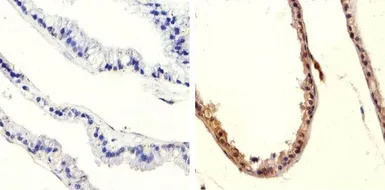

IHC-P analysis of human breast carcinoma tissue using GTX60929 PTEN (phospho Ser370) antibody.

Right : Primary antibody

Left : Negative control without primary antibody

Antigen retrieval : 10mM sodium citrate (pH 6.0), microwaved for 8-15 min

Dilution : 1:20